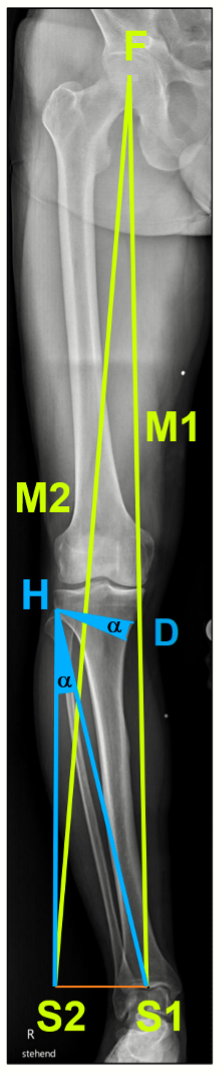

Determination of weight bearing line (Mikulicz line), MPTA (medial proximal tibia angle), mLDFA (mechanical lateral distal femoral angle) and the mechanical varus angle are the 4 key parameters of analysis in the frontal plane (Fig. 1a). The joint line obliquity (JLO) and joint line congruence angle (JLCA) are used as extended parameters for the planning of a double level osteotomy (DLO) in varus deformities on the femur and the tibia as well as the bony correction angle in any varus thrust (Fig. 1b).

Fujisawa [15] defined the ideal correction at around 35% lateral of the eminence for all grades of cartilage lesions (Fig. 1d).

We adjust the extent of the correction or the lateral shift of the weight line to the individual degree of cartilage lesions [14].

Grade 1−2 10−20%

Grade 3 20−25%

Grade 4 30−35%

With a medial open-wedge correction of the tibia, the MPTA angle should be no more than 94° after the correction, because otherwise the joint line obliquity (JLO) is more than plus 4°, which results in clinically relevant shear forces in the joint and to poorer clinical outcomes.

Cases of major correction (>10°) are almost always due to a combined deformity of femur and tibia. If the deformity is mainly on the femur, the correction must be performed at the femur. In around 10−15% of cases no acceptable joint line obliquity (JLO) can be achieved with only one correction on femur or tibia. In these cases a simultaneous double level osteotomy (DLO) correction on the femur (lateral closing wedge) and tibia (medial open wedge) should be performed [16−17].

Planning with calculation of the correction angle was performed according to Miniaci [18] (Fig. 1e). Planning can be performed either manually or using digital software. It is important when planning the bone correction angle that an abnormal joint line convergence angle (JLCA) (see Fig. 1b) is included in the planning (alpha angle minus JLCA >2°) because otherwise the osteotomy will result in an overcorrection to valgus deformity.